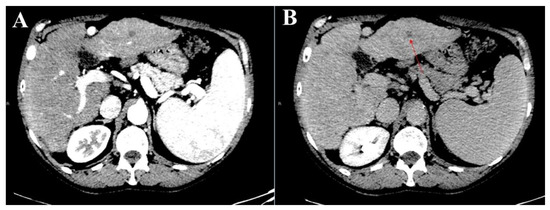

3.1. Atypical Liver Nodule Characteristics

3.2. Feasibility of Liver Biopsy

4. Discussion